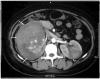

Spontaneous renal hemorrhage (SRH) is a difficult diagnostic problem with various causes. We report a case of SRH and episodic gross hematuria in a patient with metastatic choriocarcinoma involving both kidneys for which successful angioembolization was carried out for control of hemorrhage. There was no evidence of primary uterine tumor and pulmonary or liver involvement. The patient developed gastrointestinal bleeding due to jejunal metastasis while on chemotherapy and surgical resection of the involved segment was carried. However, the patient acquired nosocomial pneumonia and succumbed to sepsis in the postoperative period.